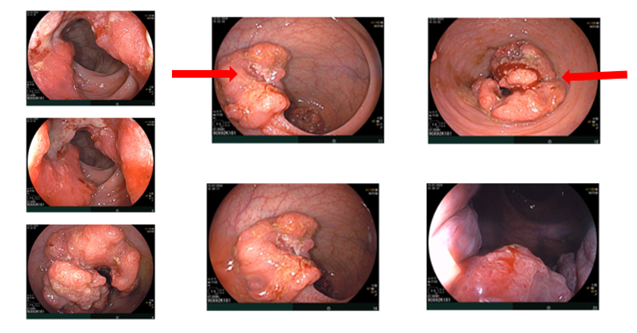

Nội soi đại–trực tràng (07/2024):

Ghi nhận hai tổn thương u sùi ở trực tràng, cách rìa hậu môn khoảng 5 cm và khoảng 10 cm. Tổn thương “phía trong” chiếm gần hết lòng trực tràng; tổn thương “phía ngoài” kích thước khoảng 3,0 cm. Ống hậu môn có đám tổn thương gồ ghề loang lổ.

Hình 1: Tổn thương u sùi ở trực tràng

Hình 2: Tổn thương gồ ghề loang lổ ở ống hậu môn